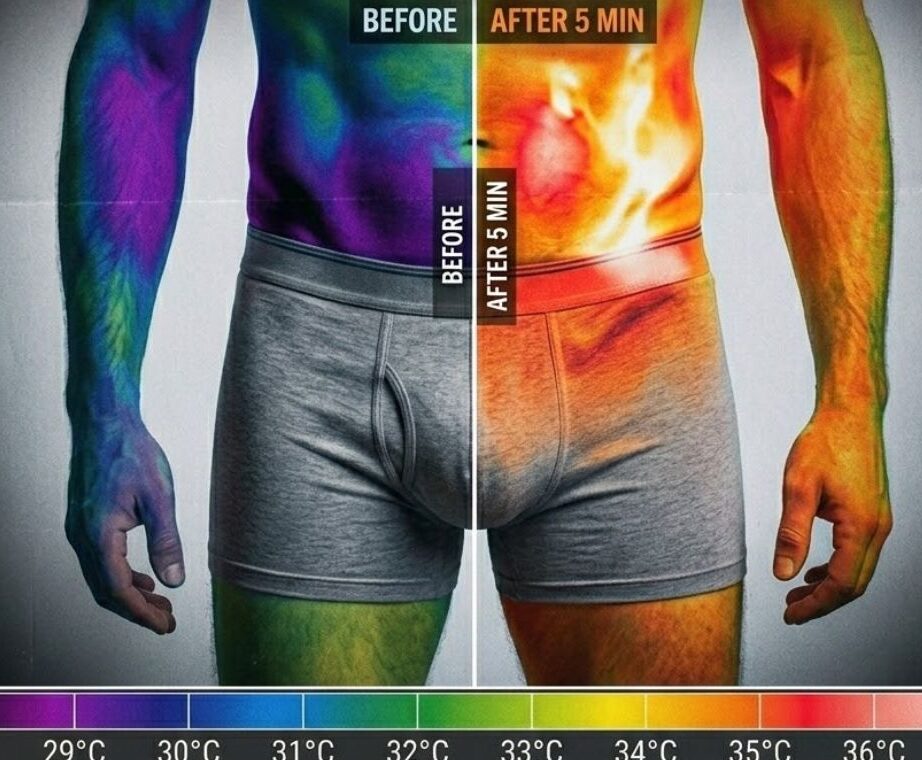

Phase 1 — Weeks 1 and 2: Activation

Dormant nerve fibres receive targeted stimulation for the first time in years. Most men report a noticeable change within the first ten days. Morning erections absent for years begin to return.Phase 2 — Weeks 3 to 5: Retraining

The nerve network begins rebuilding its response pattern. Spontaneous arousal responses return. Performance confidence begins to rebuild. The anticipatory anxiety that had built over years starts to dissolve.Phase 3 — Week 6 and Beyond: Independence

The circuit is restored. The body responds on its own — without any device, pill or assistance. No more planning ahead. No more waiting for a pill to work. Just a body that functions the way it's supposed to.